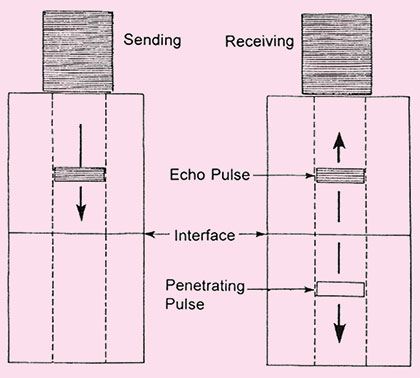

In pulse echo mode of transducer operation, a brief pulse of ultrasound is created on transducer crystal element. The ultrasound pulse that is generated by the transducer is typically 2 to 3 cycle long. These echo pulses are transmitted into the patient body. As ultrasound waves strikes various interfaces in the body as discussed earlier, some of ultrasound energy is transmitted through the interface and some is reflected in accordance with the reflective formula.

This reflective echo returns towards the transducers. These pressure wave strikes the crystal and induce a radiofrequency signal via the piezoelectric crystal (Fig. 1.3B).

Since same crystal transmit and receive ultrasound waves. So piezoelectric crystal acts a transmitter for a very brief period of time, transmitting brief pulses of ultrasound beam and rest of the crystal acts as receiver. Approximately 99 percent of the time crystal acts as a receiver and only about 1 percent of the time it acts as a transmitter of ultrasound waves.